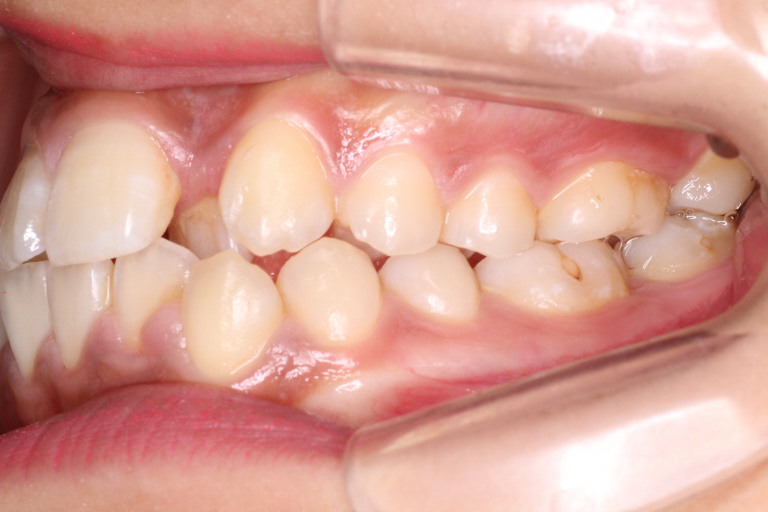

初診時のお口の中の状態です。

上の前から2番目の歯が下の歯列より内側にあり叢生です。

側方の上下の咬合関係が理想の上1本に対して下2本の理想的な噛み合わせではない。

歯列の幅がせまい。

診断:上顎前突・前歯部叢生